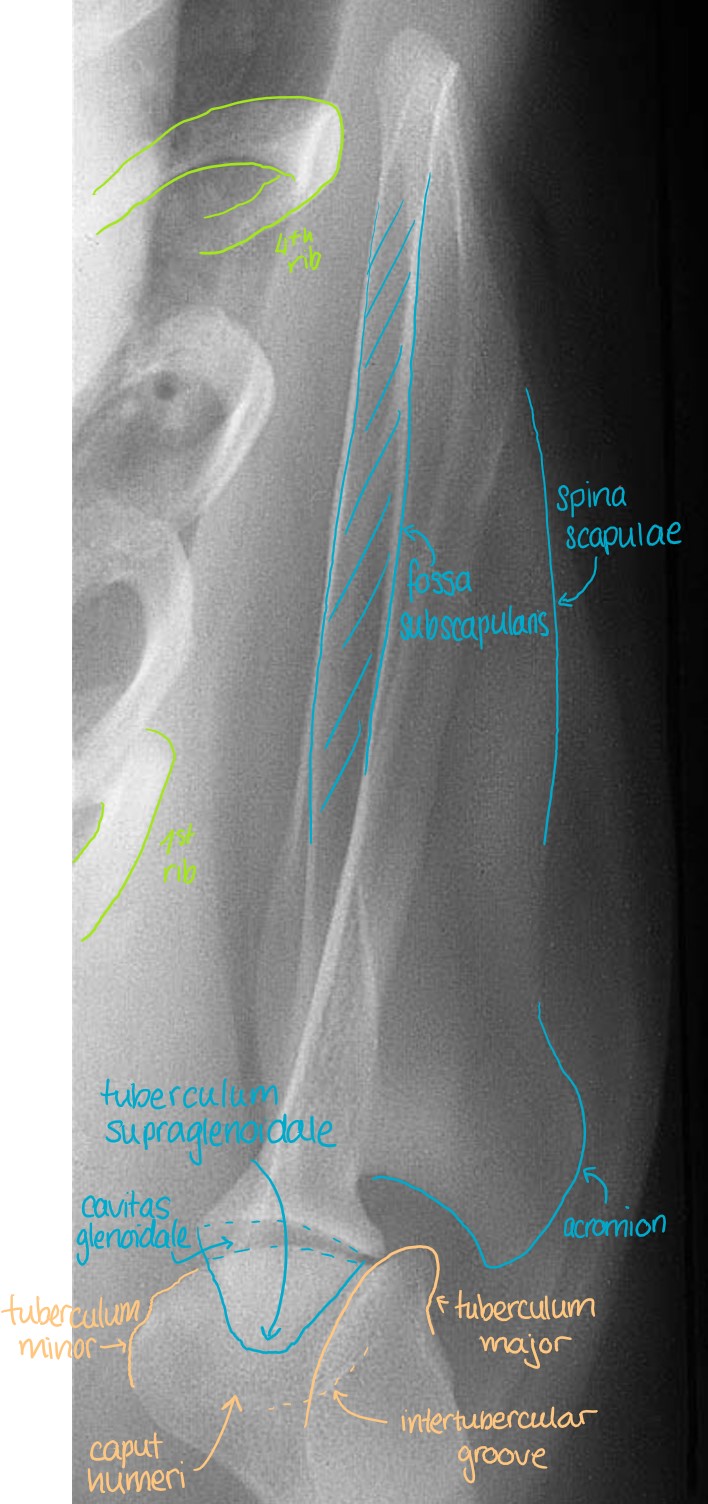

Articulatio Humeri